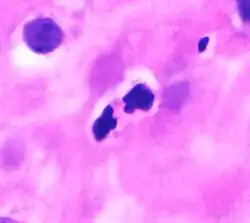

Eosinophil under the microscope (400×) from a peripheral blood smear. Red blood cells surround the eosinophil, two platelets at the top left corner. | |

These cells are eosinophilic or "acid-loving" due to their large acidophilic cytoplasmic granules, which show their affinity for acids by their affinity to coal tar dyes: Normally transparent, it is this affinity that causes them to appear brick-red after staining with eosin, a red dye, using the Romanowsky method.[4] The staining is concentrated in small granules within the cellular cytoplasm, which contain many chemical mediators, such as eosinophil peroxidase, ribonuclease (RNase), deoxyribonucleases (DNase), lipase, plasminogen, and major basic protein. These mediators are released by a process called degranulation following activation of the eosinophil, and are toxic to both parasite and host tissues.

In normal individuals, eosinophils make up about 1–3% of white blood cells, and are about 12–17 micrometres in size with bilobed nuclei.[3][5] While eosinophils are released into the bloodstream, they reside in tissue.[4] They are found in the medulla and the junction between the cortex and medulla of the thymus, and, in the lower gastrointestinal tract, ovaries, uterus, spleen, prostate, and lymph nodes, but not in the skin, lungs, esophagus, or some other internal organs under normal conditions. The presence of eosinophils in these latter organs is associated with disease. For instance, patients with eosinophilic asthma have high levels of eosinophils that lead to inflammation and tissue damage, making it more difficult for patients to breathe.[6][7] Eosinophils persist in the circulation for 8–12 hours, and can survive in tissue for an additional 8–12 days in the absence of stimulation.[8] Pioneering work in the 1980s elucidated that eosinophils were unique granulocytes, having the capacity to survive for extended periods of time after their maturation as demonstrated by ex-vivo culture experiments.[9]